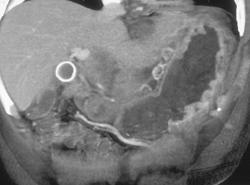

Diagnosis

Neuroendocrine Tumor